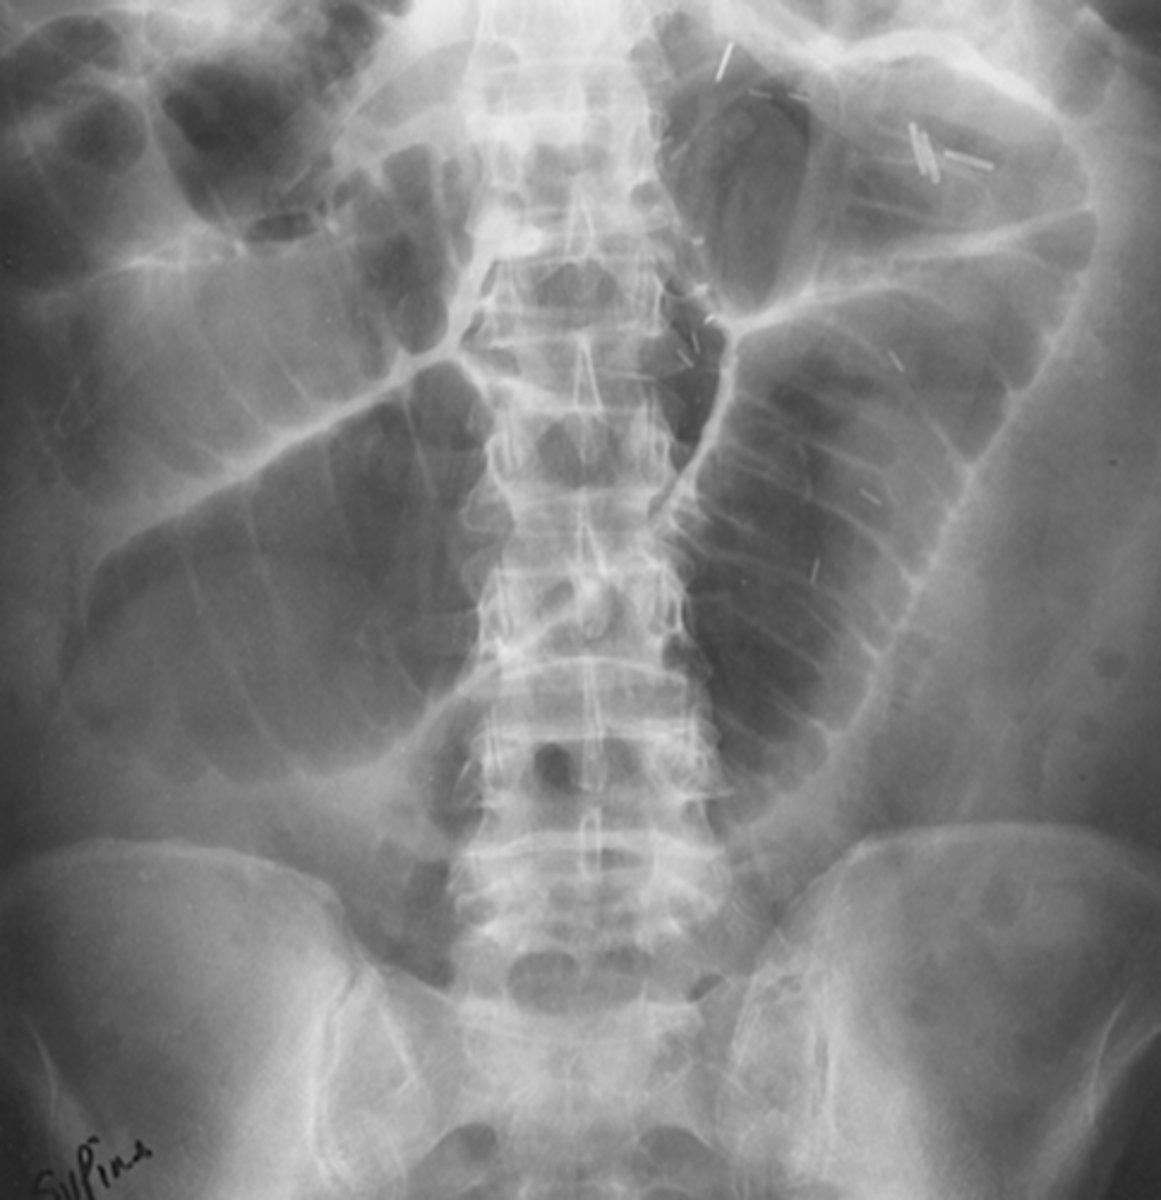

Large bowel obstruction

MC areas of LBO

cecum, hepatic/splenic flexures, sigmoid colon, upper portion of the rectum

_____ valve determines the radiographic appearance of LBOs

ileocecal

competent ileocecal valve (closed loop)

gas and feces can't reflux into small bowel, pressure builds up only in colon

incompetent ileocecal valve (open loop)

gas and fluid reflux backward into small bowel